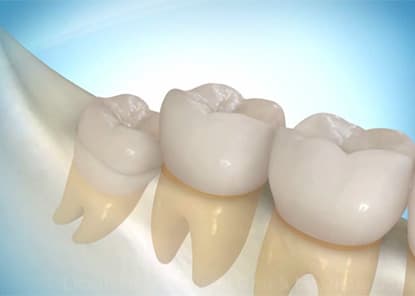

Single & Multiple Tooth Implants

Whether you are missing one tooth or several, dental implants provide the most natural and durable replacement available. Dr. Antipov places single tooth implants with immediate temporary crowns, implant-supported bridges to replace multiple adjacent teeth, and snap-on dentures (overdentures) for patients who want a removable implant-retained option. Each implant is precisely placed using 3D CT guidance and medical-grade titanium for permanent osseointegration with your jawbone.

Lifetime Results — Built to Last

Unlike bridges and dentures that need replacement every 5-10 years, titanium dental implants integrate permanently with your jawbone through osseointegration and are designed to last a lifetime. Our premium zirconia prosthetics are virtually indestructible, stain-resistant, and backed by a comprehensive warranty for lasting peace of mind.